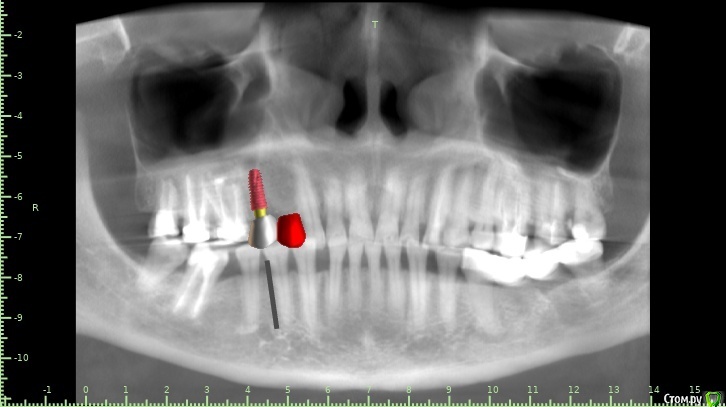

Женька Опубликовано 28 января, 2021 Поделиться Опубликовано 28 января, 2021 Что-то все спрашивают про консоли на имплантатах в области премоляров! Спрошу и я тоже.Коллеги как бы поступили в этом случае?Сам склоняюсь к консоли, но переживаю, что надо бы имплантат пошире, чтобы нагрузку нёс за двоих спокойно. Вариант с двумя винтами не нравится потому как тонковато (не очень) в области 1.4 и необходима редукция около 3мм кости. Ссылка на комментарий

Карен Аванесов Опубликовано 30 января, 2021 Поделиться Опубликовано 30 января, 2021 Что-то все спрашивают про консоли на имплантатах в области премоляров! Спрошу и я тоже.Коллеги как бы поступили в этом случае?Сам склоняюсь к консоли, но переживаю, что надо бы имплантат пошире, чтобы нагрузку нёс за двоих спокойно. Вариант с двумя винтами не нравится потому как тонковато (не очень) в области 1.4 и необходима редукция около 3мм кости.Лично я, в этой ситуации, установил бы 2 имплантата 4х8 с заглублением, в том числе с учетом того что рано или поздно с молярами придется работать. Ссылка на комментарий

Женька Опубликовано 1 февраля, 2021 Автор Поделиться Опубликовано 1 февраля, 2021 ИМХО два винта, но давайте с замерами тогдаДа, наверное вы правы, два по 3.6 проходят Ссылка на комментарий

Женька Опубликовано 5 февраля, 2021 Автор Поделиться Опубликовано 5 февраля, 2021 Я бы развел винты побольше, лучше ближе к зубам чем друг к другу, кроме того дистальный имплант можно сместить немного небнеекак-то так? 1 Ссылка на комментарий

Irouil Опубликовано 5 февраля, 2021 Поделиться Опубликовано 5 февраля, 2021 Вроде того, 5ку можно еще немного небнее и ангуляцию вестибулярнее чтобы выход шахты оставить неизменным, смысл в том, чтобы пользоваться пространством возле небного корня 6ки. Ссылка на комментарий